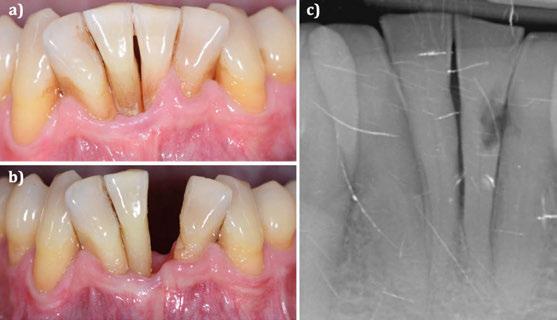

CASO CLÍNICO 2 (FIGURAS 8-15)

Paciente de 64 años de edad que acude a consulta refiriendo haber sido intervenida hace años para el tratamiento de sus recesiones gingivales. Refiere que, además, sus recesiones han progresado desde entonces.

A la exploración clínica se observan recesiones RT3 en el quinto sextante, siendo el diente en posición de 31 el que peor situación basal presenta. En este caso existe una banda de encía queratinizada

Figura 16. Caso clínico 3. a) situación clínica basal. b) situación clínica en revaluación tras terapia periodontal básica y extracción de un incisivo inferior. c) radiografía 2D inicial.

en apical que podemos pensar que se logró en la intervención previa realizada. A nivel de radiografía 3D se observa que adicionalmente presenta una dehiscencia ósea vestibular.

El diseño quirúrgico empleado es idéntico al del primer caso clínico. En este caso, adicionalmente, se desplaza la banda de encía queratinizada apical hacia coronal gracias al avance del colgajo.

Al combinarse la presencia de recesiones gingivales avanzadas con pérdida de inserción interproximal y dehiscencias óseas se utilizó nuevamente una lámina de cortical desmineralizada. La sutura realizada en este procedimiento quirúrgico es idéntica a la del primer caso clínico.

En un seguimiento a medio plazo, se puede observar un mantenimiento adecuado de los resultados en términos de salud periodontal, cobertura radicular, aumento de encía queratinizada y de profundidad de vestíbulo.